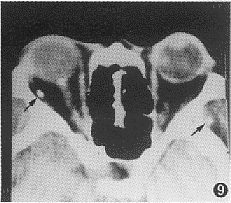

9 CT检查眶内囊尾蚴病 (非活动期) , 右侧外直肌及左侧颞窝内两斑点状致密影 (箭头) , 为囊尾蚴死亡后的钙化斑